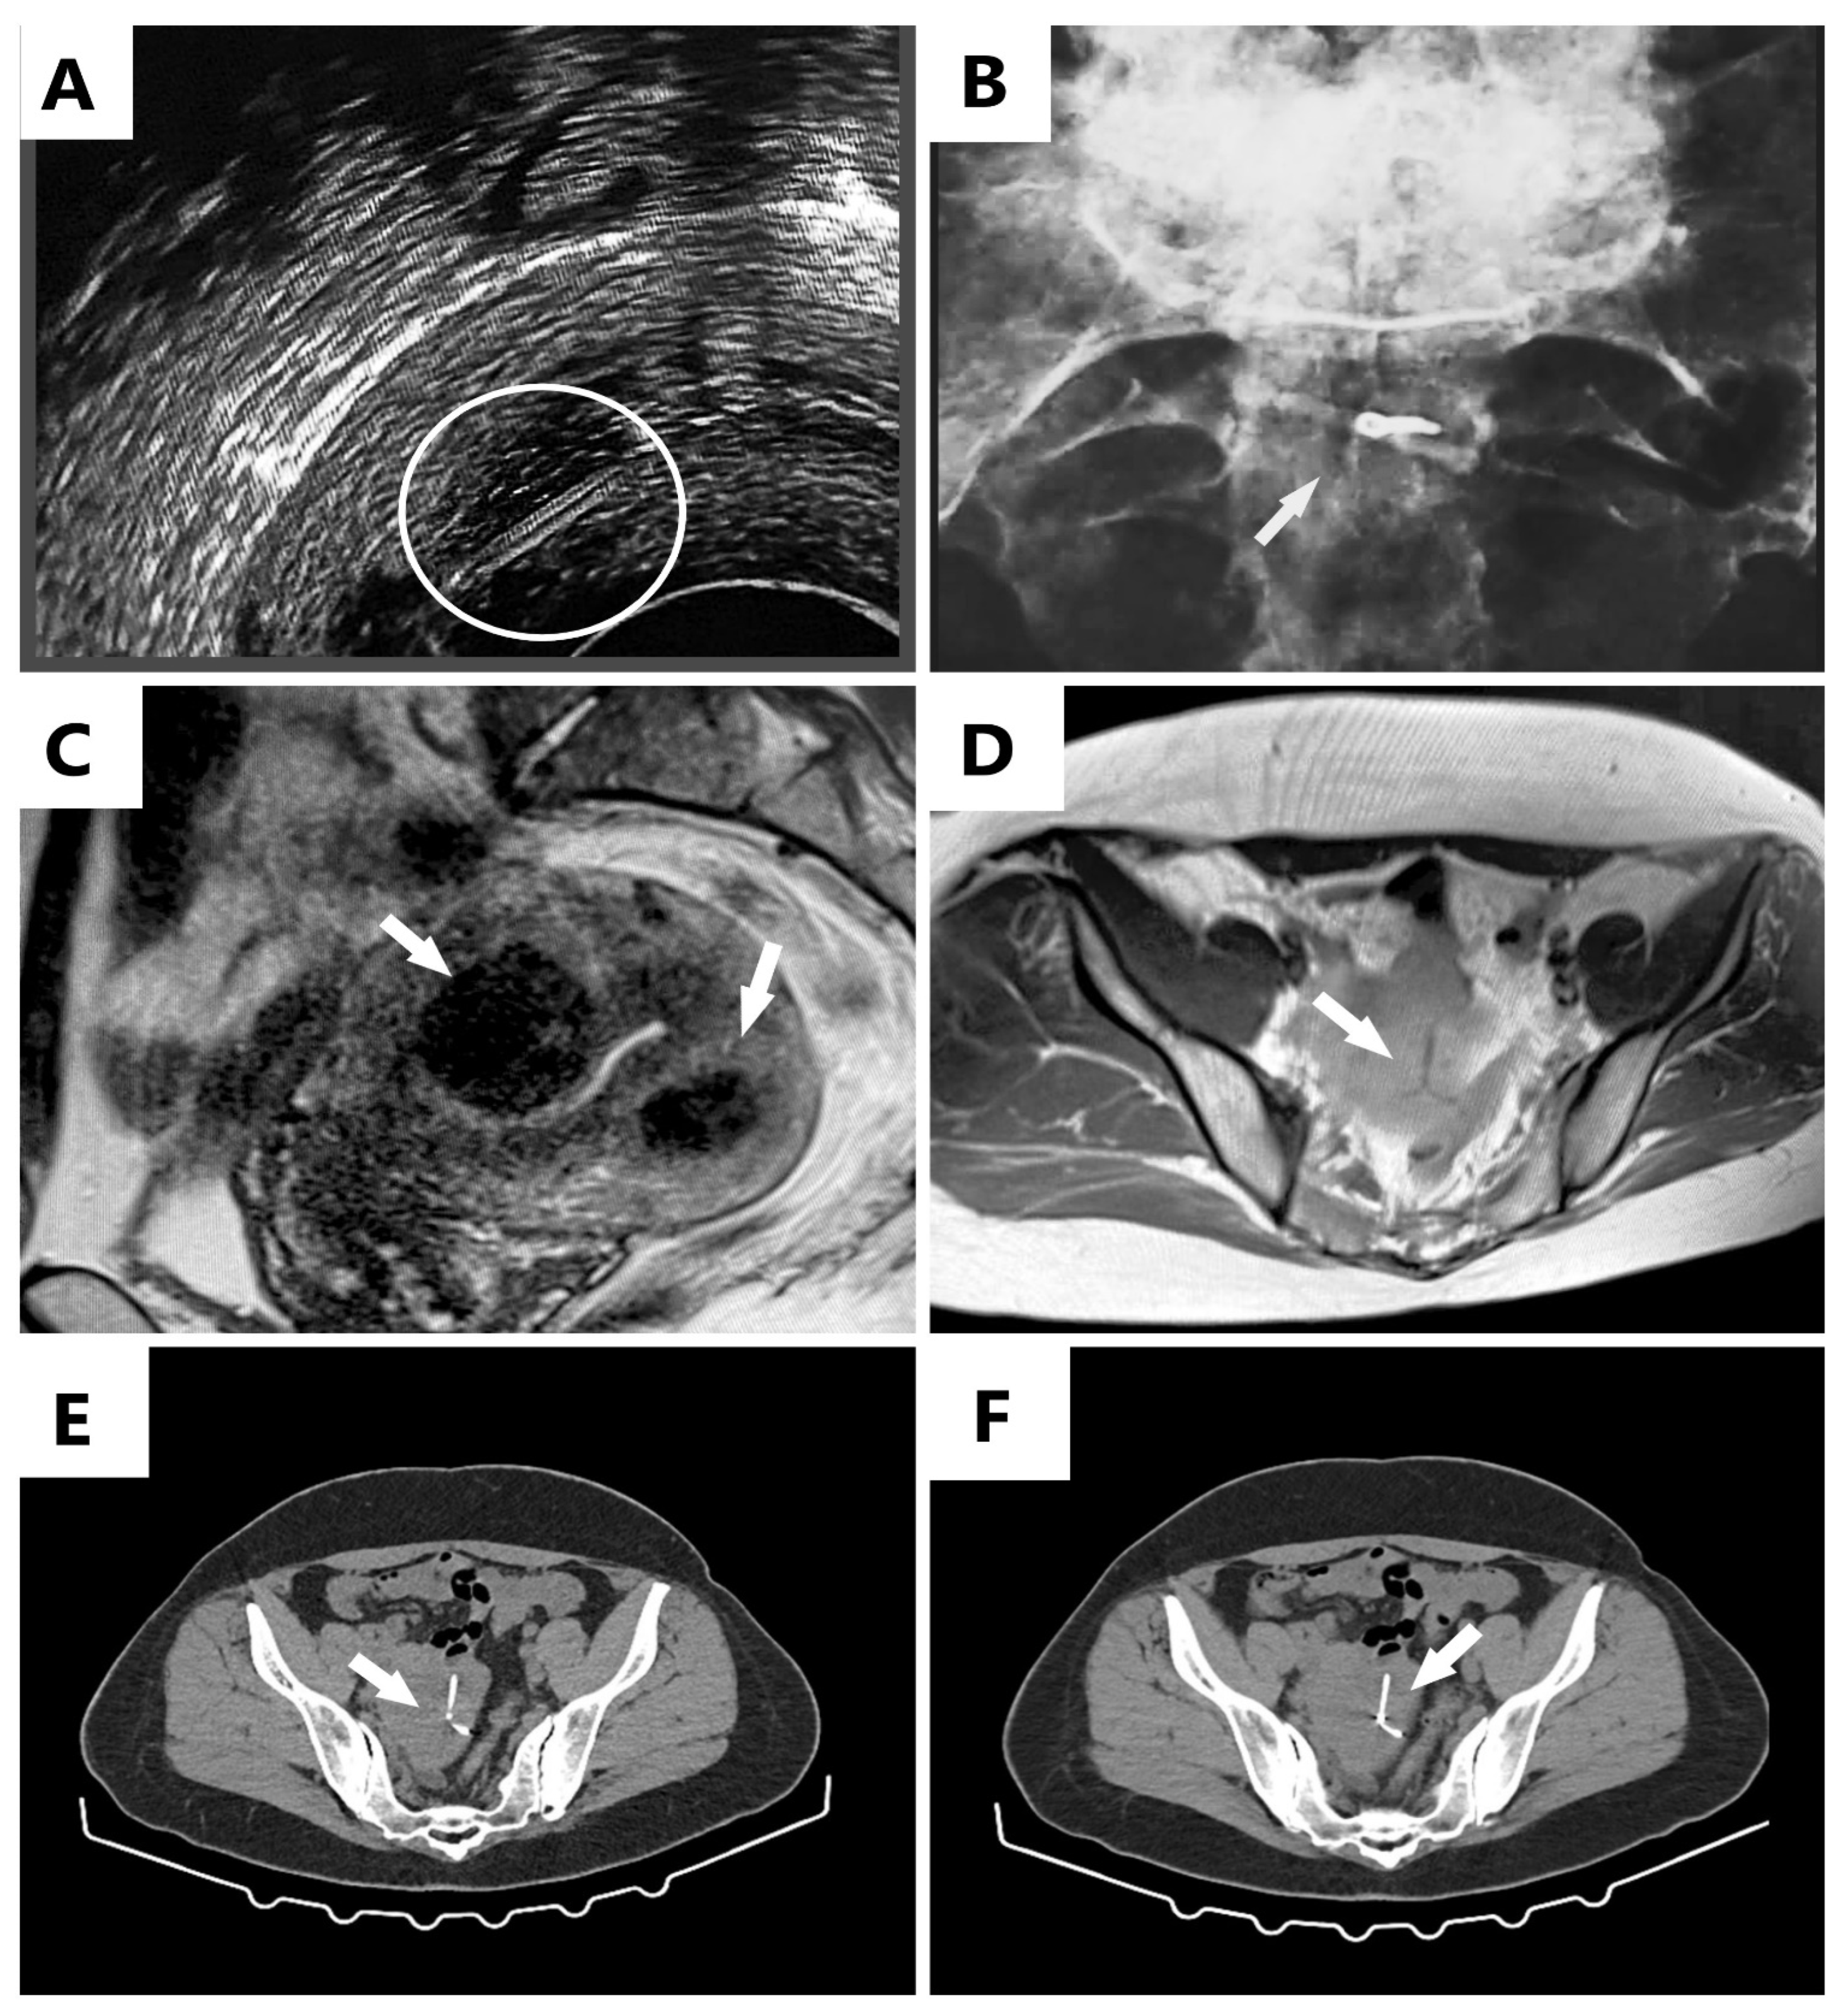

An Interesting Image of Transmural Migration of a Levonorgestrel-Releasing Intrauterine Device (LNg-IUD)

Mitranovici, M.-I.; Chiorean, D.M.; Sabău, A.-H.; Cocuz, I.-G.; Tinca, A.C.; Mărginean, M.C.; Popelea, M.C.; Irimia, T.; Moraru, R.; Mărginean, C.; et al. An Interesting Image of Transmural Migration of a Levonorgestrel-Releasing Intrauterine Device (LNg-IUD). Diagnostics 2022, 12, 2227. https://doi.org/10.3390/diagnostics12092227